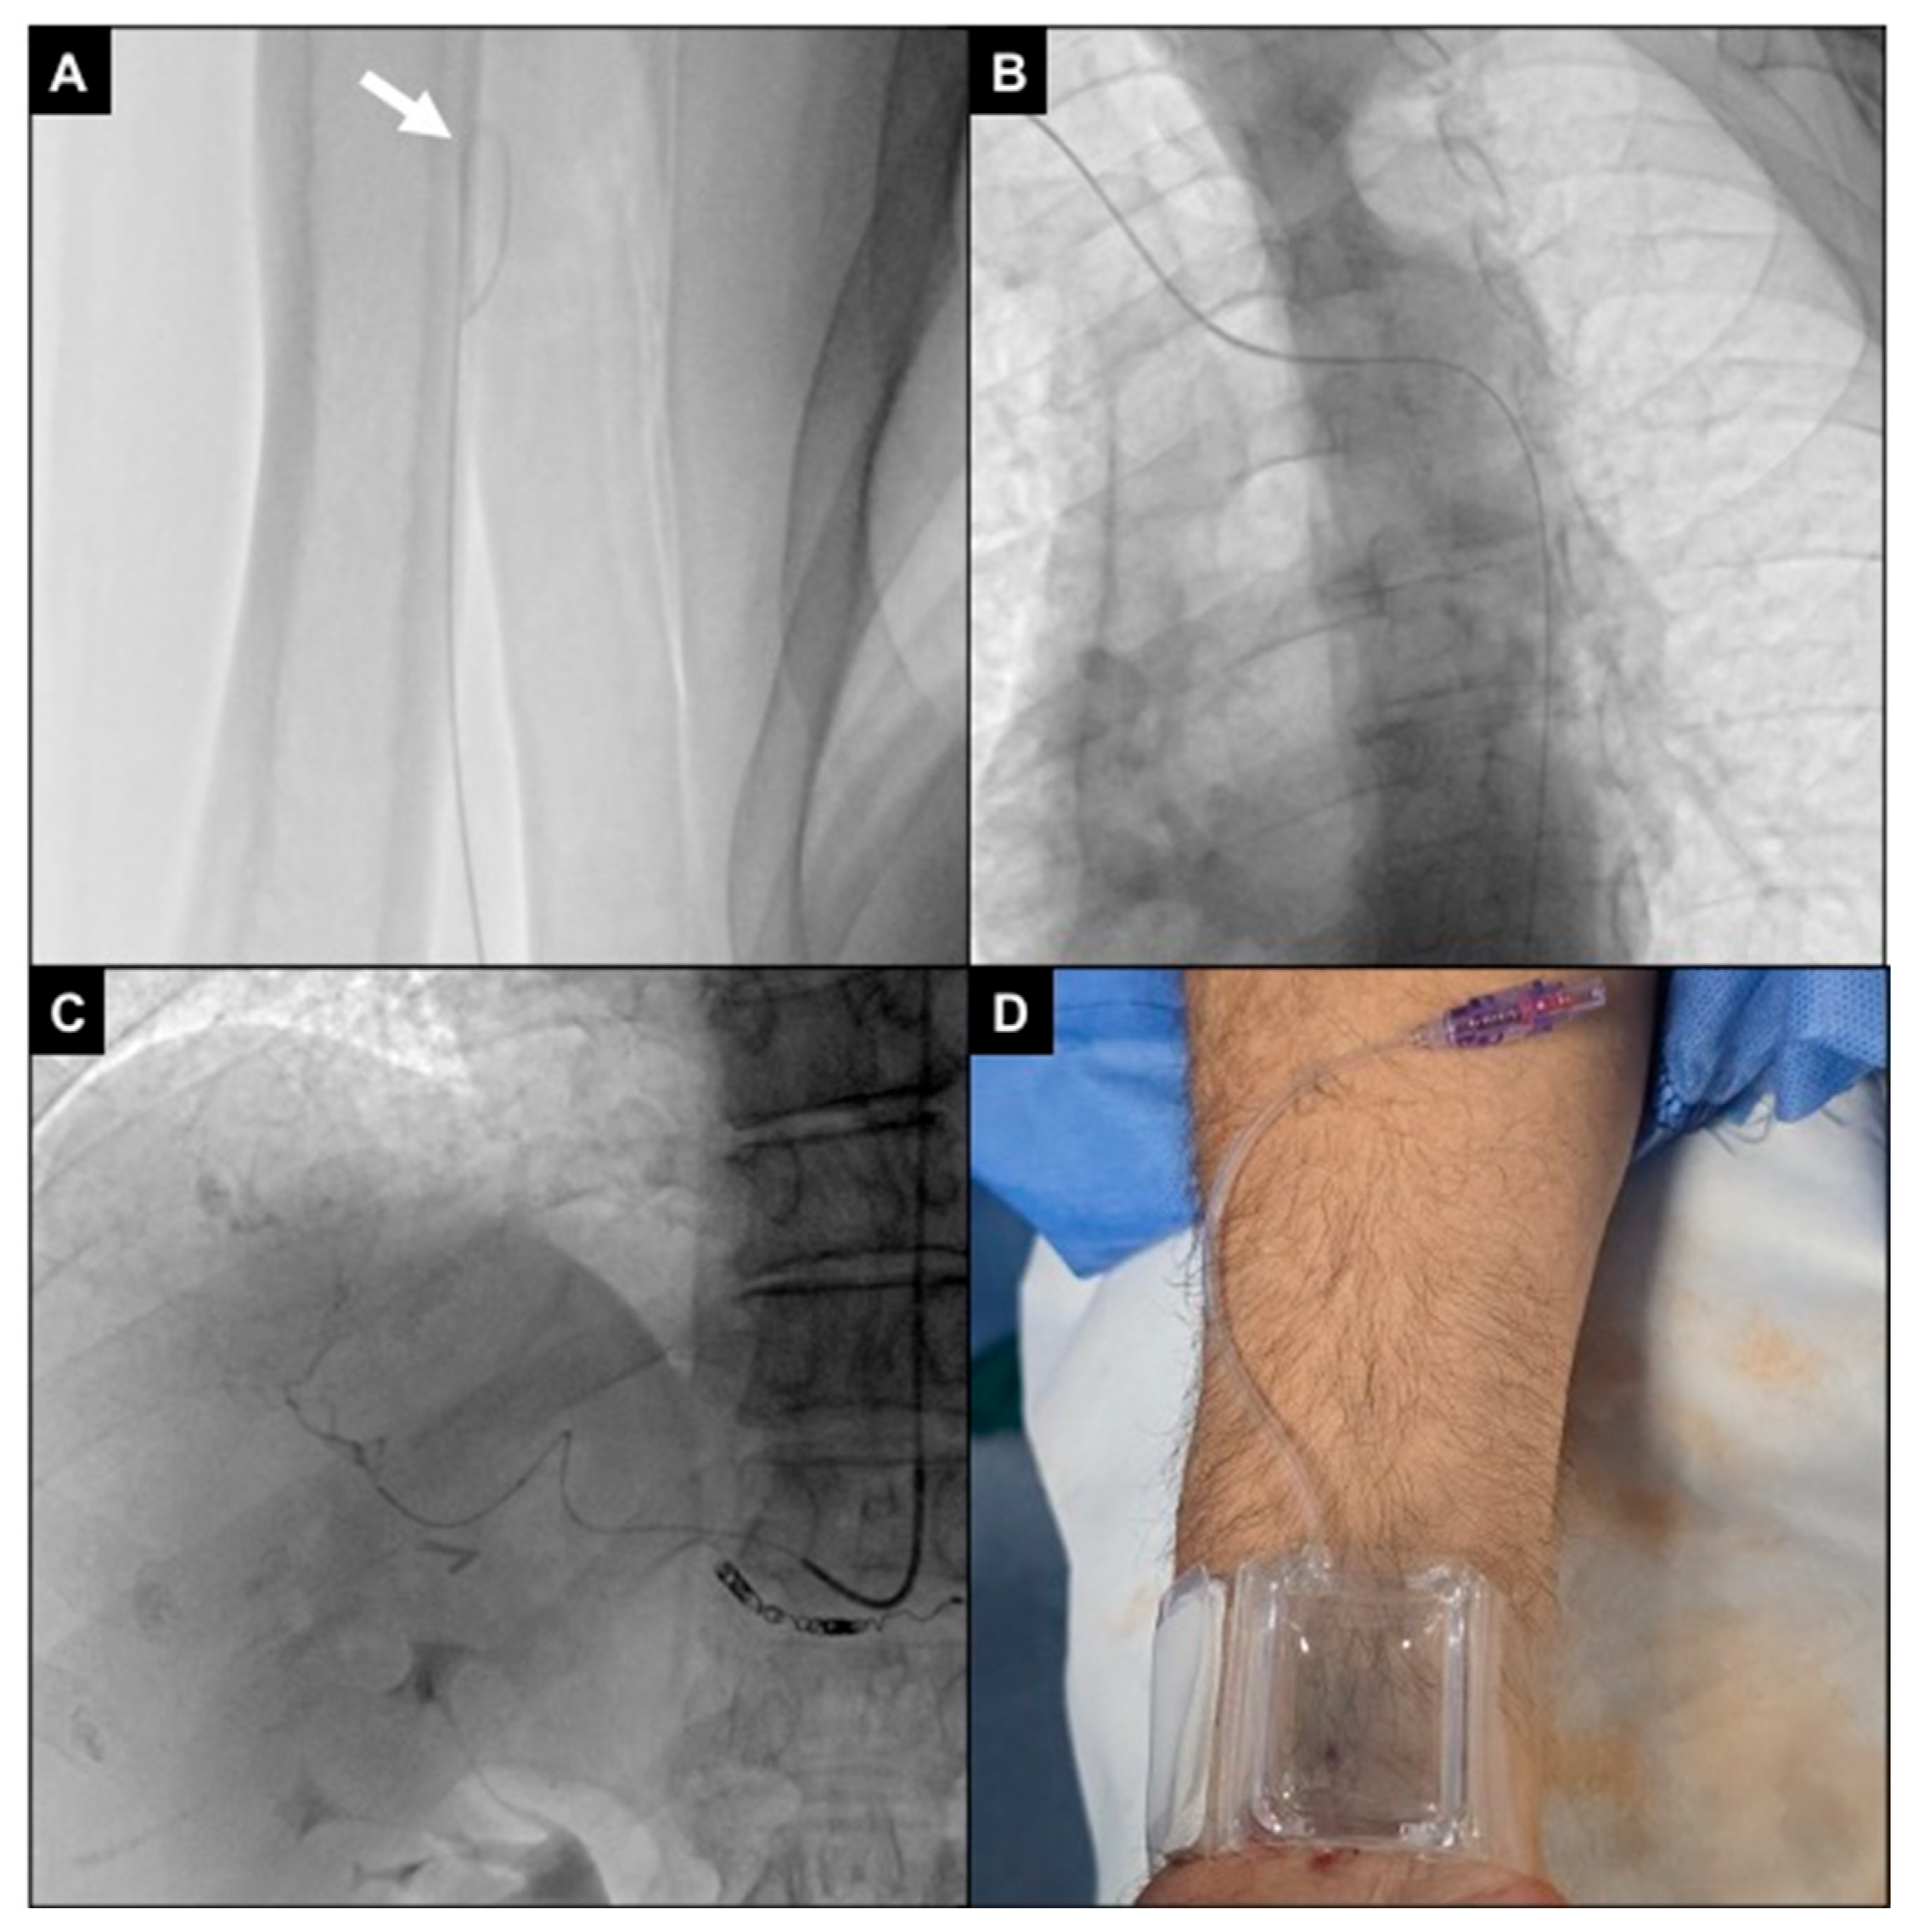

Finally, a transparent sterile patch was used to fix the introducer and avoid displacements during the procedure (Figure 4).

Figure 4.

Right radial access. (A) Patient positioned head first, with the right arm parallel to the trunk and the wrist turned volar and hyperextended, with right femoral access sterilized and ready in case of need for crossover; (B) 1 mL of local anesthesia injected via a 25 g needle subcutaneously, lateral to the radial artery at the level of the styloid process; (C) right radial artery punctured with a 21 g needle with a .021″ 45 cm nitinol guidewire advanced inside; (D) fluoroscopic control showing proper guidewire positioning without collateral engagement, with compression of the access point before inserting the introducer; (E) a second mL of local anesthesia injected subcutaneously to reduce pain related to sheat positioning; (F) the 5Fr 10 cm introducer was placed and fixed to the skin with a transparent patch.